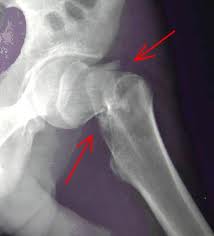

HIP fracture care at Lynn’s Queen Elizabeth Hospital has been rated among the best in the East of England.

The hospital scored top marks for that particular type of orthopaedic care in the 2011 report from the National Fracture Database, published last week.

It revealed that hip fracture patients at the QEH are not only treated swiftly – more than 80 per cent are admitted to an orthopaedic ward within four hours, one of the best results in the region – but after-care is good too.

Only 0.7 per cent of QEH patients were found to have suffered pressure ulcers, also known as bed sores, during their stay – a figure only marginally bettered by a hospital in Hertfordshire.

Patients also have the best chance of having a hip replacement following a fracture with 100 per cent in this category receiving replacements – putting the QEH in joint first place in the region along with Peterborough District Hospital.